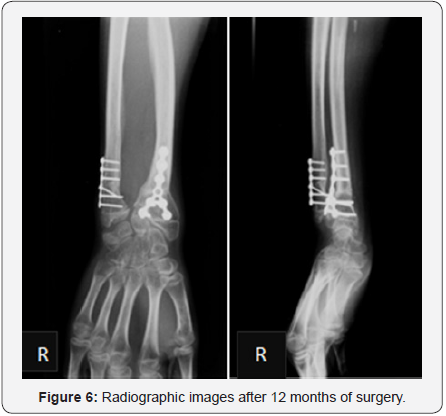

Osteotomies were protected with dorsal forearm plaster splint for 3 weeks. Postoperative management depends on what is done. Cast immobilization may be necessary for some weeks after an osteotomy of the radius or ulna. Physiotherapy may be necessary in children who are not able to regain range of motion on their own after 2-3 months without restrictions. In our case no physiotherapy was needed. After 12 months, there was no pain, a good aesthetic and mobility improvement of the right wrist, mainly of prone-supination (Figure5). The radiographic images (Figure 6) showed good alignment and healing of the bone.